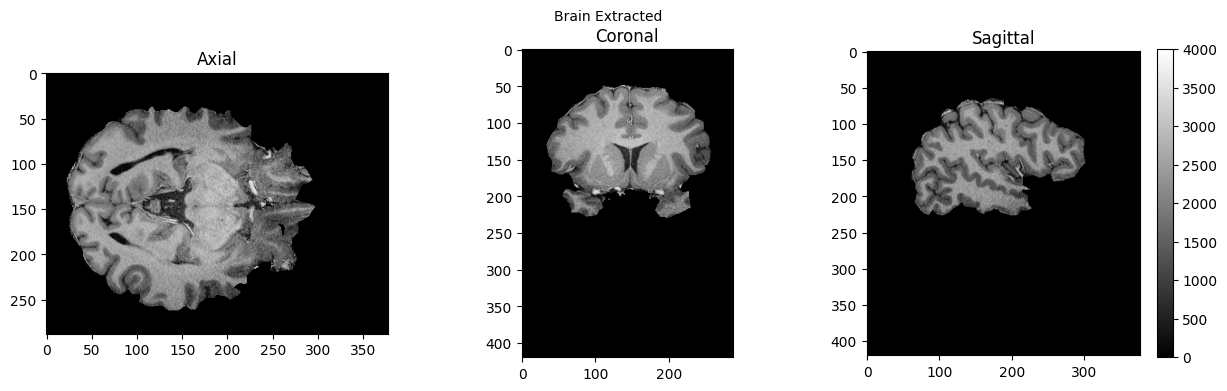

brain = nib.load('./sub-01_ses-01_7T_T1w_defaced_brain.nii.gz').get_fdata()

view_slices_3d(brain, slice_nbr=230, vmin=0, vmax=4000, title='Brain Extracted')